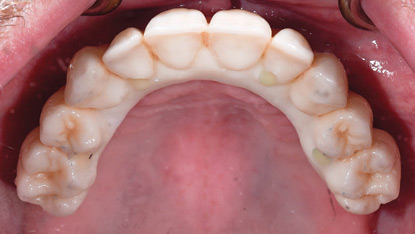

Alternative Verification Jig for the Assessment of Mandibular Flexure

PATIENT: M, Age: 62, ASA II (pharmacological management of hypertension and high cholesterol). CHIEF COMPLAINT: Patient presented for the fabrication of a mandibular implant supported fixed prosthesis, with implants having been placed 6 months ago. CLINICAL FINDINGS: Maxillary arch had a fixed implant supported prosthesis with implants in the 17, 16, 14, 13, 22, 23, … Read more